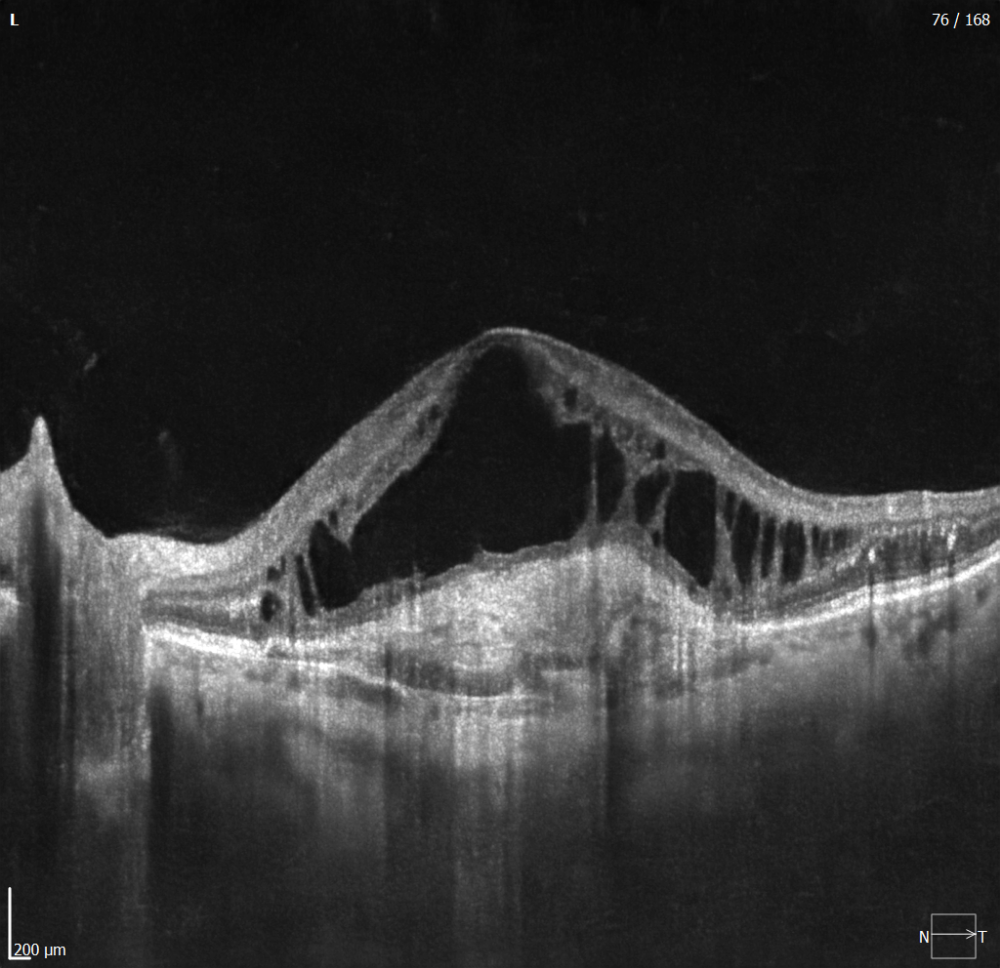

- Analyse Chambre Antérieure.

- Acquisitions Ultra grand champ.